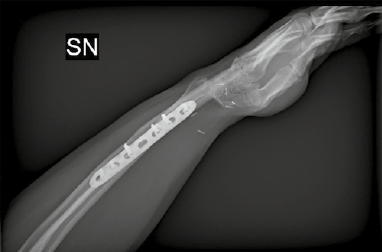

Overall, the choice between arthrodesis and joint-preserving procedures should be individualized, balancing oncologic safety with functional expectations. Factors such as tumor grade, local bone involvement, patient age, occupational demands, and long-term priorities play a decisive role in guiding reconstruction strategy 6,9,14. This tailored approach ensures that surgical management not only secures tumor control, but also provides the most functional and durable outcome for each patient. In Figures 1-3 we present an example case of 28-year-old man with a distal radius GCT resected after denosumab medical treatment and reconstructed with an arthrodesis with microsurgical free fibula (Tab. IV, Figs. 1-3).

Figure 2.Resection and reconstruction with an arthrodesis with microsurgical free fibula (AP view).